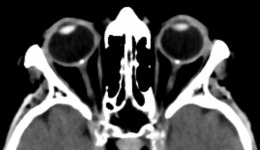

Computed tomography (CT)

Optic disc drusen will show calcifications on CT, although it is not routinely used for diagnosis. CT may also detect a mass causing true papilledema or enlargement of the ventricles.